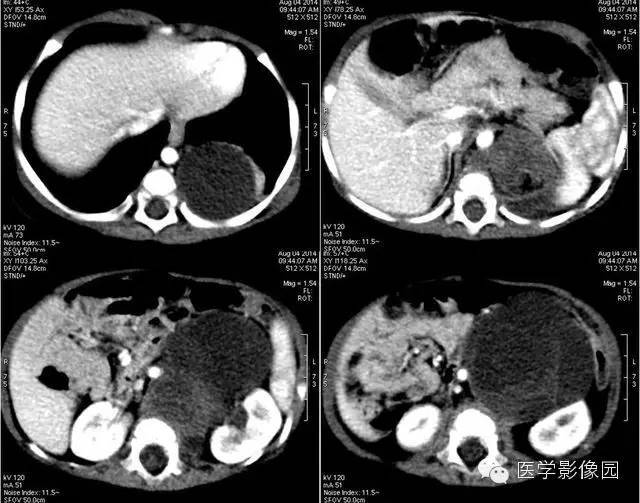

1——平扫

2——增强

3——增强

4——增强

小儿畸胎瘤好发于身体中线及两旁,多发生在骶尾部、腹膜后、纵隔、卵巢等部位,是腹膜后常见的实体瘤之一,发病率仅次于肾母细胞瘤和神经母细胞瘤。

畸胎瘤是由两个或三个原始胚层组织演化而来的胚胎性肿瘤,大体上囊性、实性或囊实性兼有。囊性畸胎瘤又称皮样囊肿,仅含表皮及其附属成分,基本上均为良性。实性畸胎瘤含有三个胚层成分。按组织学分类可分为良性畸胎瘤和恶性畸胎瘤。良性畸胎瘤由分化良好的成熟组织构成,故又称为成熟畸胎瘤,瘤体囊性部分多于实质部分,小儿中绝大部分均为良性畸胎瘤。恶性畸胎瘤由胚胎发生时期的未成熟组织构成,实质部分常多于囊性部分,恶性畸胎瘤在小儿中十分少见。小儿畸胎瘤以女性多见,男女之比约为1:3-4,腹部包块和腹胀为腹膜后畸胎瘤主要的临床表现,患儿一般状况良好。

恶性畸胎瘤瘤体以实体为主,病变边界模糊不清,可侵犯周围组织,肿块大小对鉴别良恶性意义不大。